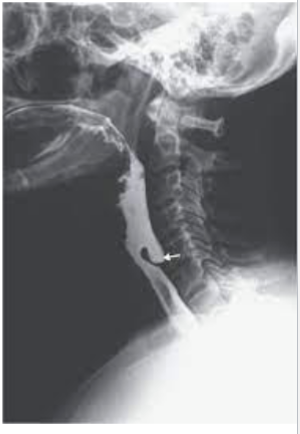

What is this

Zenkers Diverticulum